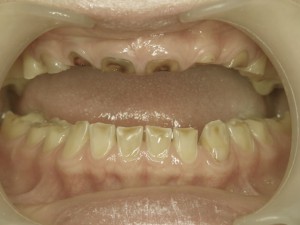

こちらの前歯の被せ物は歯茎が退宿してしまったことにより適合が悪くなってしまい

また、歯と歯の間にすき間もできてしまって審美的にもすきっ歯にみえます。

このような状態のままにしておくと審美面だけの問題だけではなく、歯茎と被せ物の隙間に汚れ(プラーク)が残りやすくなるため虫歯や歯周病の原因にもなってしまいます。

いきなり新しい被せ物を入れるのではなく最初は仮歯を入れて様子をみていきます。

また歯と歯の間のすき間をなくすために

仮歯で調整していきながら隙間をなくしていきます。

こちらの写真は仮歯の状態です。

歯と歯の間を調整したことにより隙間がなくなりました。

まだ最終的な被せ物は入っていないため完成したお写真をお見せできないのですが、

この仮歯の段階でもかなり改善されました。

歯茎のラインと仮歯の際に隙間はなく、歯と歯の間の隙間もなくなりました。

あとは歯茎に炎症が残っていないか確認し、問題なければ型取りをし、被せて完成になります